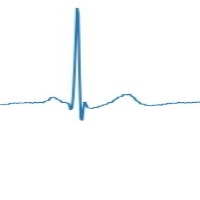

Couplet Computer Vision Project

Cardiac Monitoring: Couplet can be incorporated into patient monitoring systems to detect the various types of couplets in real-time, allowing healthcare professionals to identify arrhythmias and other cardiac anomalies. Early intervention can lead to better patient outcomes.

Telemedicine: Couplet can be integrated into telemedicine platforms to remotely assess a patient's electrocardiogram (ECG) signals. This helps improve access to care for patients who live in rural or hard-to-reach areas, allowing physicians to review their ECG and determine if there are any issues that require immediate attention.

Wearable Device Analysis: Couplet can be embedded into wearable health devices, such as smartwatches or fitness trackers, to analyze ECG data in real-time. This can help users monitor their heart health and alert them to any abnormalities, encouraging proactive healthcare management.

Medical Research: Couplet can be used by researchers studying the prevalence and causes of various couplet types. Automating the identification process can save time and improve accuracy, allowing researchers to focus on understanding the underlying mechanisms and developing effective treatments.

Medical Training and Education: Couplet can be applied to educational materials and training modules, helping medical students and professionals learn to identify different couplet types. By automating the recognition process, trainees can test their skills and gain confidence in their ability to diagnose conditions related to couplet classes.